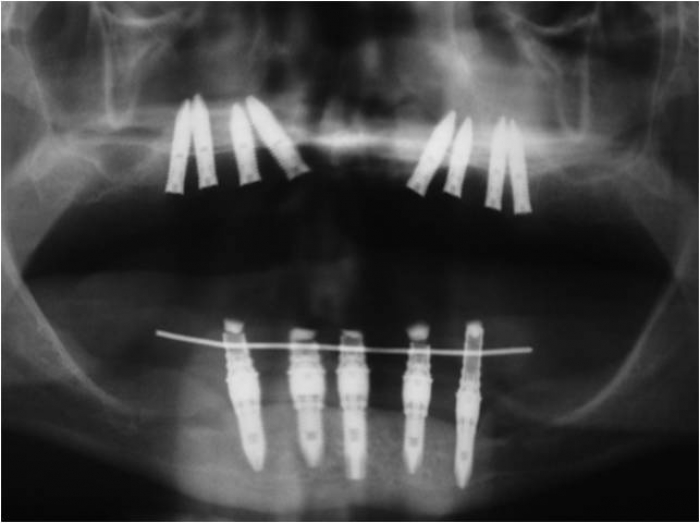

Rx do enxerto ósseo de maxila, com osso de crista ilíaca

Rx dos implantes Cone Morse superiores